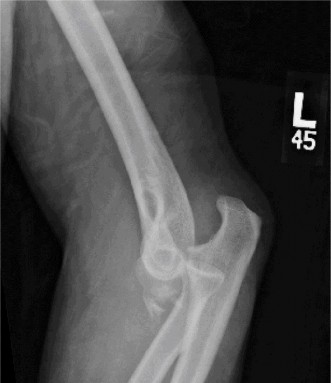

Understand the outcome and prognosis of adhesive capsulitis? CASE 30 Dr. Robert J. Stewart A 44-year-old, right-hand-dominant male with well-controlled diabetes and hypertension presents to clinic with left shoulder pain. The patient denies a history of trauma or injury. He localizes his pain over the superolateral aspect of the shoulder, and it radiates to the deltoid insertion. He has experienced pain over the past few months, but it has progressively become more severe over the past several days. He has difficulty sleeping and with range of motion because of severe pain. While examining the patient, he has a warm and tender left shoulder, and while performing a range of motion evaluation, the patient notes that he has a sensation of “catching.” He has a positive Hawkins sign, negative drop arm test, and pain with a cross body adduction test. A radiograph of the left shoulder is shown in Figure 2–77.

Figure 2–77

Discussion

The correct answer is (D). Calcific tendonitis (CT) is a condition characterized by the buildup of calcium hydroxyapatite crystals within tendons. It typically occurs around synovial joints and has been reported in the hip, paraspinal muscles, hand, and foot. It most frequently occurs around the shoulder in patients who are 30 to 50 years old. No one over the age of 71 has been recorded having this condition. Degenerative calcification and reactive calcification have both been proposed as mechanisms for the deposition of calcium. Although the etiology is not understood, most believe that it is a reactive mechanism involving an active, cell-mediated process in a viable tendon. The cell-mediated process has been divided into three distinct phases: precalcific, calcific, and postcalcific. Depending on the stage, imaging, and physical examination characteristics can differ. The calcific stage can be further classified into three phases: formative, resting, and resorption. Rotator cuff arthropathy is seen in older patients with chronic, massive, rotator cuff tears and glenohumeral osteoarthritis. Septic arthritis can look similar to CT, but this patient has had a history of shoulder pain without fever or other risk factors for infection. Answers C and E are incorrect because there are no signs of osteoarthritis of the AC or GH joint on radiograph or physical examination.

Which structure is most likely to be affected on the basis of the information obtained thus far, including the radiograph Figure 2–77?

The correct answer is (C). Calcific tendonitis (CT) is most often localized in the supraspinatus tendon. Radiographic views should include a true AP in internal and external rotation, axillary, and scapular-Y to evaluate for calcium deposits in the tendons of the rotator cuff. There are no reports of the deltoid muscle being involved in CT. Radiographs also help to distinguish resorptive and formative phases. Two radiographic types have been described: Type I (associated with the resorptive phase and acute pain) is a deposit that is fluffy or fleecy in appearance with a poorly defined periphery. Type II (associated with the formative phase and chronic pain) has discrete, homogeneous deposits that have a well-defined periphery.